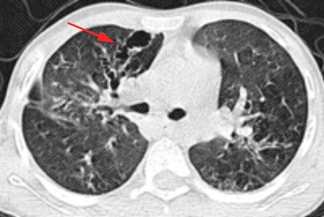

Texto alternativo para a imagem Créditos: Dra. Elazir Mota - Rio de Janeiro/RJ.

Descrição das imagens: Paciente infantil do sexo masculino, 11 anos, exame de acompanhamento de fibrose cística. Na tomografia computadorizada do tórax, observam-se extensas bronquiectasias varicosas bilaterais, mais evidentes à direita (setas vermelhas).

• Tomografia computadorizada do tórax: A fibrose cística cursa principalmente com espessamento das paredes brônquicas e bronquiectasias. As bronquiectasias podem ser varicosas, cilíndricas ou císticas; geralmente são bilaterais e predominam nos lobos superiores. A impactação mucoide, o preenchimento das pequenas vias aéreas e as consolidações também são achados frequentemente encontrados.